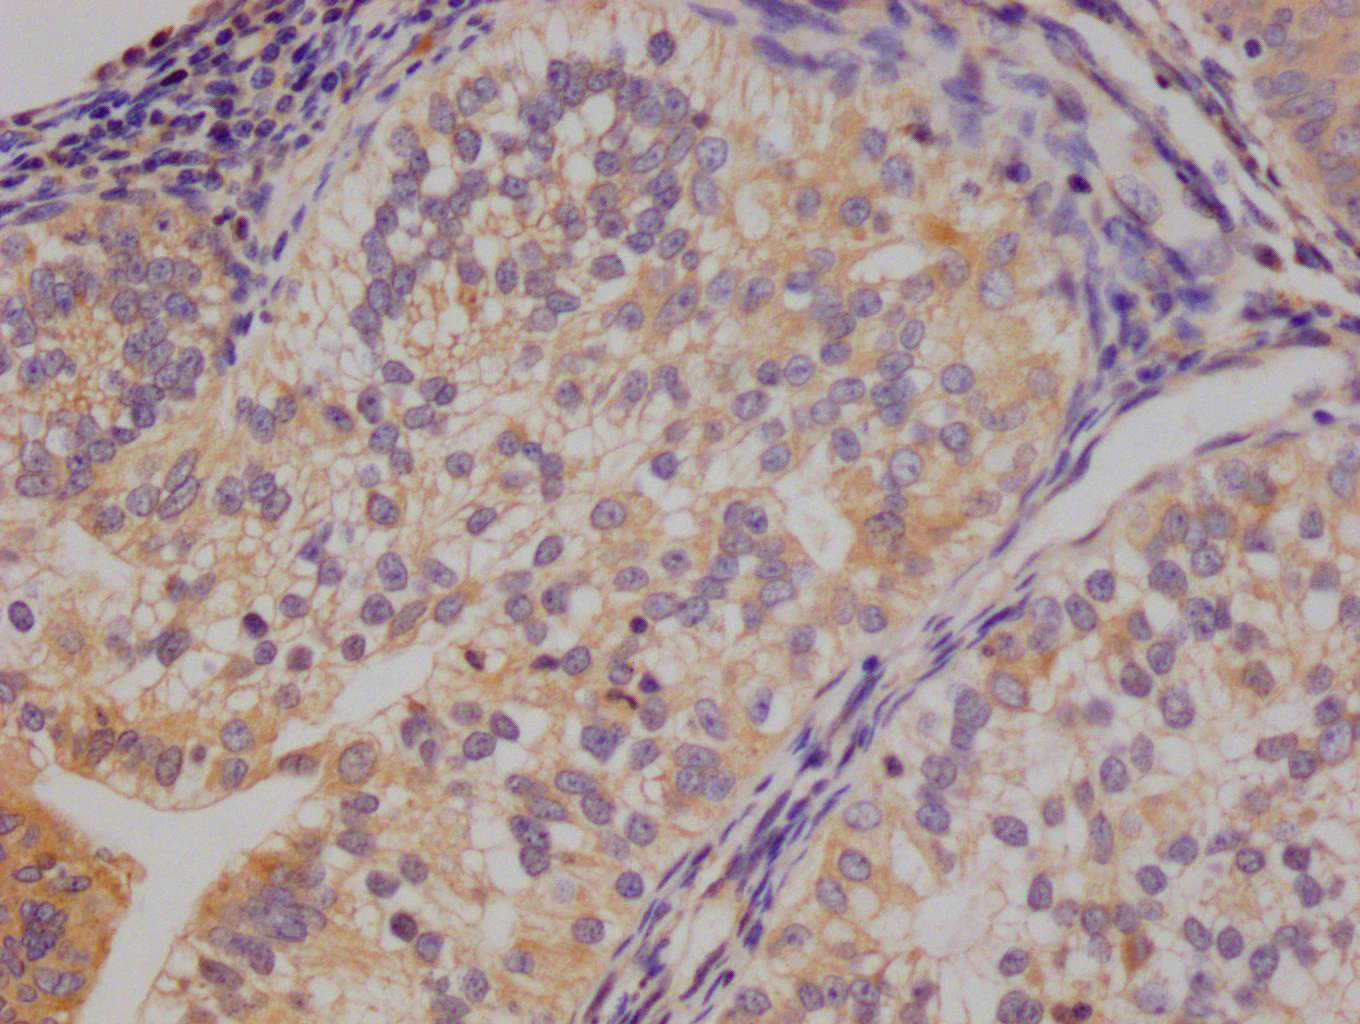

Immunohistochemistry of paraffin-embedded human placenta tissue using CSB-PA854079ESR1HU at dilution of 1:100